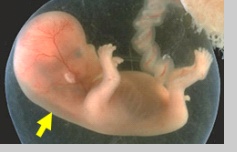

Translucenza NucaleLa translucenza nucale (NT) è la manifestazione ecografica dell’accumulo sottocutaneo di fluido dietro il collo fetale nel primo trimestre di gravidanza.

Viene utilizzato il termine “translucenza” indipendentemente dal fatto che presenti setti al suo interno, che sia confinata al collo fetale o che ricopra interamente il feto

• Anomalie di sviluppo del sistema di drenaggio linfatico.

Uno dei possibili meccanismi coinvolti nell’aumento della NT è rappresentato dalla dilatazione del sistema linfatico giugulare, secondaria ad un ritardo nello sviluppo delle connessioni vascolari con il sistema venoso. Altre ipotesi sono legate ad una dilatazione linfatica primitiva o ad una proliferazione dei canali linfatici con conseguente alterazione del flusso diretto verso il sistema venoso.